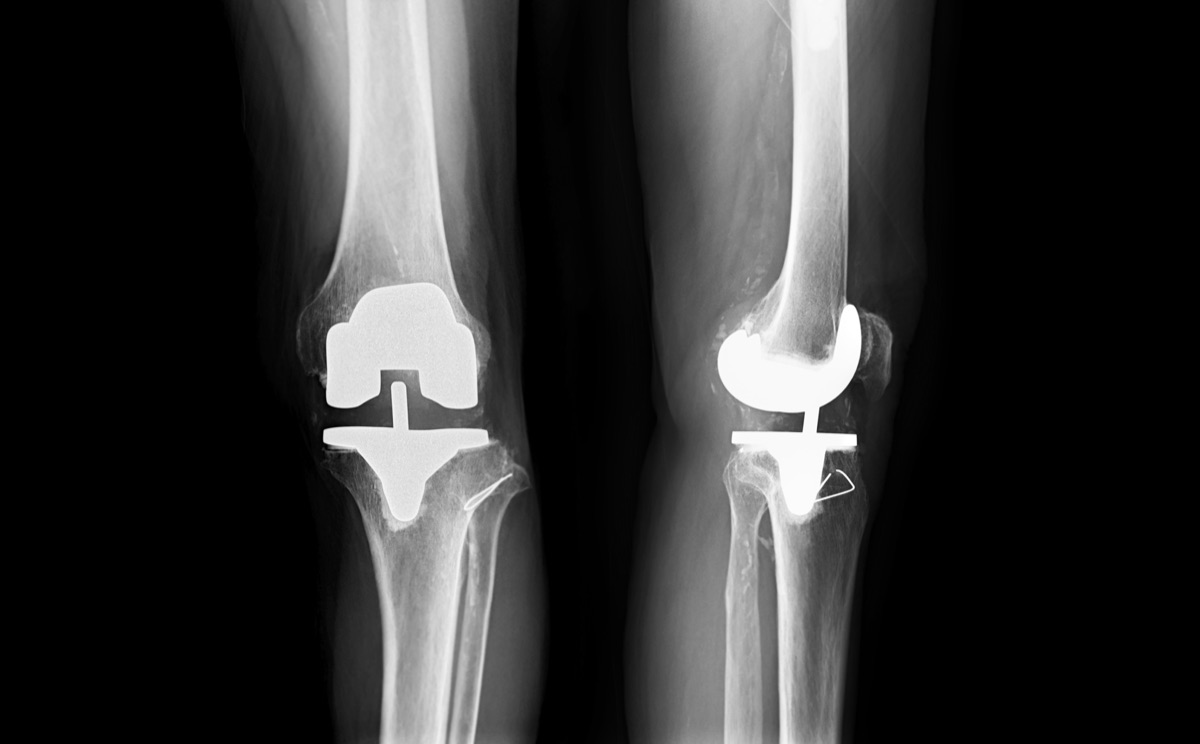

The knee is the largest joint in your body, formed by three bones—the femur (thighbone), tibia (shinbone), and patella (kneecap). These are connected by ligaments, cushioned by cartilage, and surrounded by the joint capsule.

Knee replacement becomes necessary when cartilage protecting the joint wears away, causing bone-on-bone contact that leads to severe pain and limited mobility.

The most common type, replacing all three compartments of the knee. Ideal for patients with widespread arthritis affecting the entire joint.